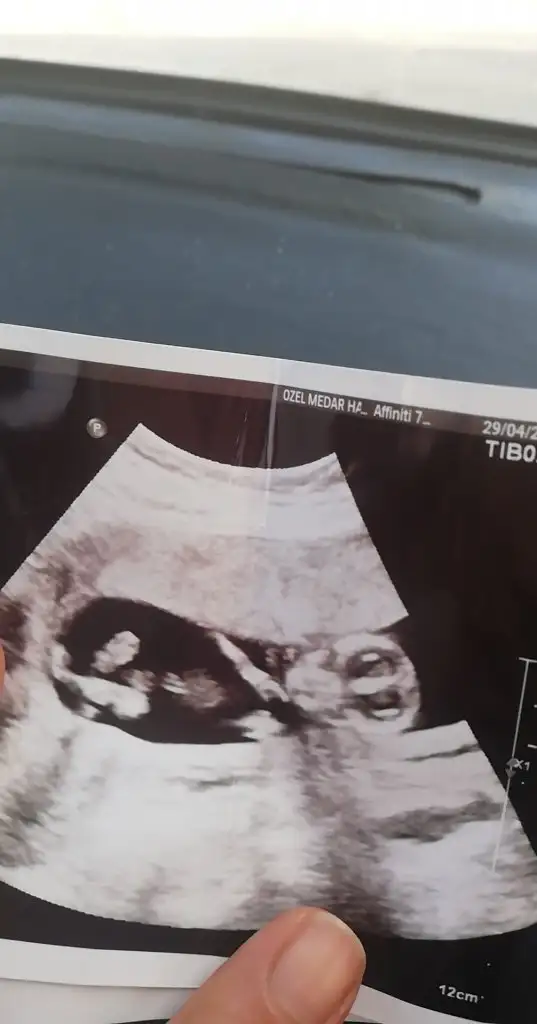

Merhaba lütfen tahmin yaparmısınız 2 yıl öncede yapmıştınız tutmuştu :)))

• 20210502_063913.webp

20210502_063913.webp

14,9 KB · Görüntüleme: 58

• 20210502_063853.webp

20210502_063853.webp

13,6 KB · Görüntüleme: 62